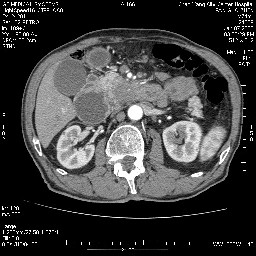

女,74岁,呕吐10余日

壶腹部的占位性病变,考虑为十二指肠癌并梗阻,但脾内多发性低密度区为转移吗?

还有胃、脾之间可见有侧支循环建立。左肾盂积水。

考虑来源于十二指肠水平段的恶性占位,侵及周围组织,特别是胰腺,可见区域淋巴结肿大,左侧下腔静脉畸形。

十二指肠水平段腔内占位伴梗阻,中等度较为均匀的强化,洗脱慢,区域淋巴结显示增多,符合腺癌表现。下腔静脉变异。

十二指肠降段扩张,水平段狭窄成鼠尾状,肠壁明显增厚,胰腺勾突增大成不均匀强化,其内可见低密度区,胆囊增大,1十二指肠水平段腺癌侵犯胰腺勾突可能大,2胰腺癌侵犯十二指肠(只有胆囊增大没有肝内外胆管扩张不好解释)代除外.

上消化道造影见十二指肠结节状充盈缺损,ct增强十二指肠壁局限性增厚并强化,考虑十二指肠壶腹癌?

十二指肠降段扩张,水平段狭窄成鼠尾状,肠壁明显增厚,胰腺勾突增大成不均匀强化,其内可见低密度区,胆囊增大,1十二指肠水平段腺癌侵犯胰腺勾突可能大,2胰腺癌侵犯十二指肠 。

今日手术结果:胰腺钩突癌侵犯十二直肠,腹腔淋巴结转移.